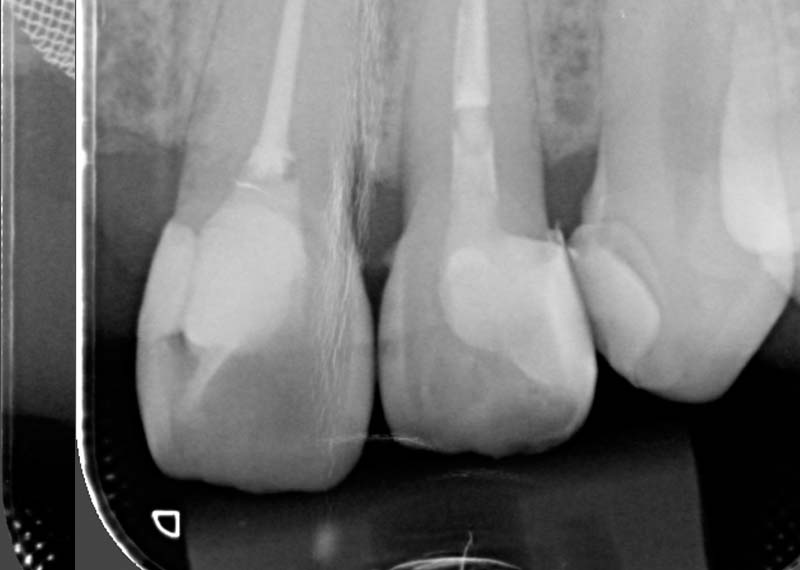

Sometimes the problem goes deeper than what we can see. When bacteria reach the inner nerve of the tooth, it can cause persistent pain or infection.

A root canal treatment (RCT) aims to remove the infection, relieves your pain, and saves your teeth.

For: Compromised pulp (decay or cracked tooth)

We strive for single visit whenever possible